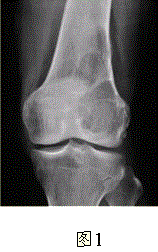

问题 患者女,35岁,左膝关节隐痛1年余,近1周加重,活动后明显疼痛。查体:左股骨下端外侧肿胀,压痛。行左膝关节正侧位CR,并行左膝关节CT扫描,见下图。 依据此病变的CT表现,以下说法正确的是

选项 A.病变边缘清晰 B.CT示左股骨外髁骨皮质不完整,提示病变为恶性或生长活跃 C.病灶内部密度不均 D.病灶周围可见软组织肿胀,提示为炎性病变 E.病灶无明显硬化缘 F.病灶呈中心性生长

答案 ABCE

解析 ABCE